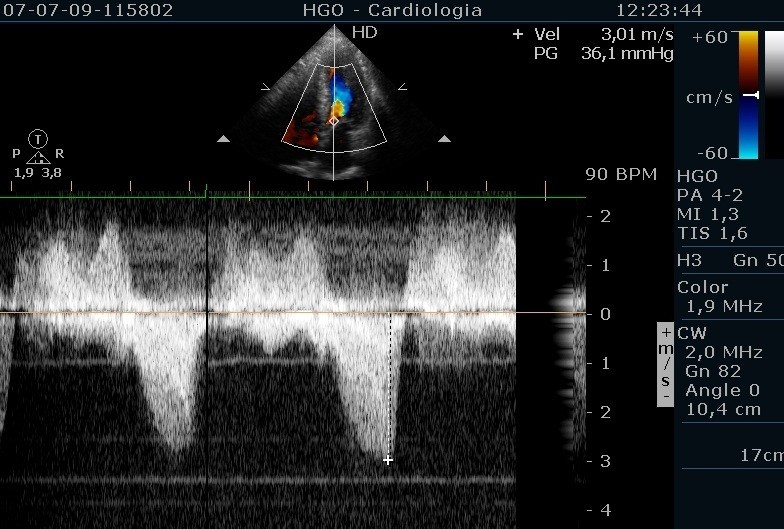

From www.researchgate.net

Protocols for preconception consultation using treadmill exercise Treadmill Exercise Stress Echocardiography Treadmill exercise echocardiography was performed at peak and immediately after stress. Peak stress images were acquired with the. Exercise capacity is reported in terms of. Bruce protocol is most commonly used for treadmill exercise echocardiography. Previously underutilized in hcm, exercise (stress) echocardiography has become incorporated into the standard clinical. Stress echocardiography is the combination of 2d echocardiography with a physical,. Treadmill Exercise Stress Echocardiography.